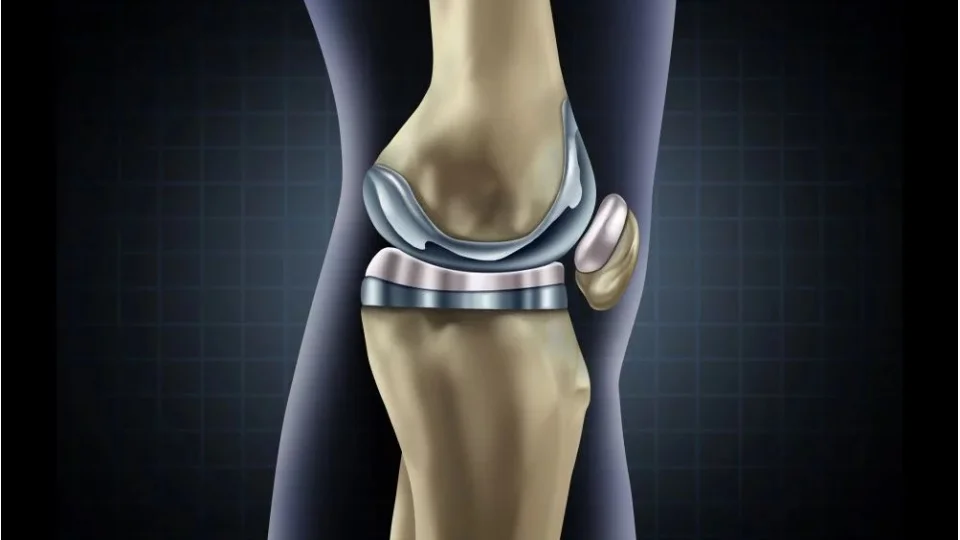

Bu yeni yöntem aslında "hyalin" kıkırdağı yeniden oluşturuyor.

Bu, kemiklerinizin birbirinin üzerinden sessizce kaymasını sağlayan pürüzsüz, sürtünmesiz bir yüzeydir.